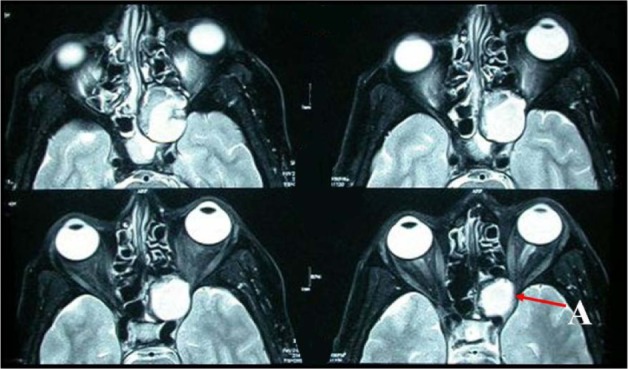

Figure 4.

Preoperative serial axial magnetic resonance imaging shows large T2 weighted hyperitense lesion at the sphenoedmoidal region compressing and displacing the left optic nerve at the orbital apex (A) and intracranial extension.